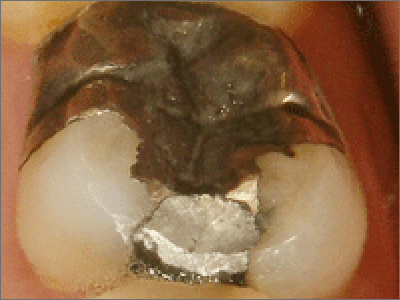

歯との適合が悪くなり、内部で虫歯が進行しているケースも

非常に多いのが実情です。

症状が出ていたら「少しずつでも金属除去」を

もしお口の中に、

- 古い銀歯

- 大きな金属の被せ物

- 境目が黒くなっている詰め物

がある場合は、

症状が強くなる前に少しずつ交換することをおすすめします。

before